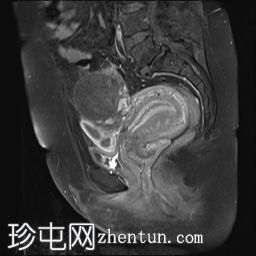

冠状位

T1加权像

可见子宫外腹腔内妊娠囊,内含胎儿组织。

该妊娠囊向后推移子宫,并与剖宫产瘢痕凹陷处紧密相连。

该妊娠囊与相关肠袢无法分离。可见其与性腺血管密不可分,且性腺血管明显突出。

胎盘位于妊娠囊后方,紧贴子宫前壁。

沿妊娠囊下缘可见一处异质性局灶性积液,最大轴向尺寸约为 8.4 × 5.5 cm,T1 加权像呈异质性高信号,T2 加权像呈异质性中等信号,T1 脂肪抑制序列未见信号下降,提示为血液成分。该积液压迫膀胱。

子宫体积增大,后倾,子宫内膜厚度约 1 cm,子宫下段前壁可见局灶性变薄(既往子宫瘢痕)。子宫连接区完整,未见肌层肿块。可见子宫内膜腔边缘有血性分泌物。